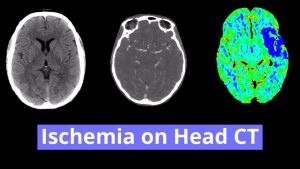

- Global cerebral volume loss with sequela of chronic small vessel disease

Global cerebral volume loss with sequela of chronic small vessel disease. Intracranial atherosclerosis.